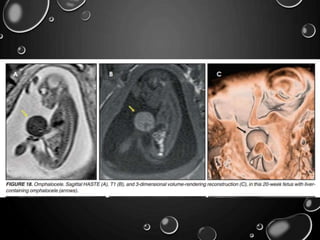

OMPHALOCELE

• OMPHALOCELE IS A MIDLINE DEFECT OF THE ABDOMINAL WALL AT

THE SITE OF ATTACHMENT OF THE UMBILICAL CORD.

• THE EXTRUDED ORGANS ARE COVERED BY PARIETAL PERITONEUM.

• BOWEL, LIVER, AND STOMACH MAY PROLAPSE TO THE OMPHALOCELE

SAC.

• OTHER ANOMALIES : CHROMOSOMAL ABNORMALITIES (TRISOMY 13

AND 18) BECKWITHWIEDEMANN SYNDROME; INTESTINAL ATRESIAS

AND ABNORMAL FIXATION OF THE BOWEL, ARE COMMON.

• CAREFUL FETAL SURVEY IS WARRANTED TO EVALUATE THE

COEXISTENCE OF ADDITIONAL CONGENITAL ABNORMALITIES.